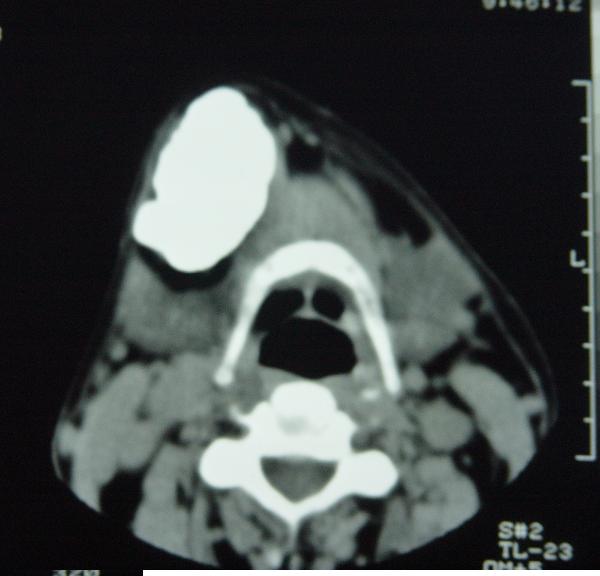

标题: CT12465:下颌骨肿瘤,请会诊 [打印本页]

标题: CT12465:下颌骨肿瘤,请会诊

发现下颌骨肿瘤近30年.逐渐增大.

考虑右侧下颌骨水平部及升部骨纤维异常增殖症可能性大。

造釉细胞瘤,没有特征性;半月切迹?骨间隔?多房性骨密度减低区,大小不等。鉴别;动脉瘤样骨囊肿,骨软骨瘤。本人,更倾向于---骨软骨瘤。

考虑右侧下颌骨骨化性纤维瘤。